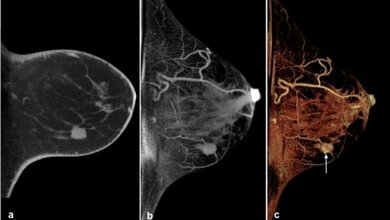

Bei der MRT-Brustkrebsvorsorgeuntersuchung wird die Durchblutung des Gewebes gemessen. Das Verfahren ist sehr genau, in manchen Fällen ist es allerdings schwer zu sagen, ob entdeckte Knoten bösartig sind, oder ob das Gewebe nur besonders dicht und daher gut durchblutet ist. Ein zweites MR-Verfahren, die DWI, stellt die Bewegung von Wassermolekülen in Strukturen dar und kann sie durch den Diffusionskoeffizienten (ADC) auch objektiv messen. Das Studienteam führte nun anschließend an die herkömmliche MRT noch eine DWI durch.

Paola Clauser, Universitätsklink für Radiologie von MedUni Wien und AKH Wien, Mitglied des Comprehensive Cancer Center (CCC) der beiden Einrichtungen und Erstautorin der Studie: „Mit Hilfe der DWI können wir Läsionen viel besser charakterisieren. Denn: Im gesunden Gewebe ‚tanzen‘ die Wasserstoffmoleküle schneller als bei bösartigen Tumoren. Karzinome weisen eine hohe Zelldichte auf und hindern die Wassermoleküle bei ihrer Bewegung. Wir konnten nun belegen, dass wir Brusttumoren, wenn der Grenzwert (ADC) größer gleich 1,5+10-3 mm2/s ist, nicht biopsieren müssen.“

Die DWI dauere maximal drei Minuten, verbessere aber die Diagnose erheblich. Pascal Baltzer, Universitätsklink für Radiologie von MedUni Wien und AKH Wien, Mitglied des CCC und Studienleiter sagt: „In dieser multizentrischen Studie ist es uns mit diesem Grenzwert gelungen, einen objektiven, standardisierten Biomarker zu etablieren. Er ist überall anwendbar, weil er weitgehend vom Gerät, der Erfahrung der Radiologen/-innen, der Messzeit oder dem Messverfahren unabhängig ist.“ Die DWI ist in der Diagnose von Schlaganfällen bereits lange etabliert und erfreut sich auch in der Tumordiagnostik steigender Beliebtheit. Jede radiologische Einrichtung ist daher in der Lage, sie durchzuführen. Baltzer fährt fort: „Unsere Erkenntnis ist diagnostisch sofort verwertbar. Dafür braucht es kein Spezialzentrum – jede niedergelassene Radiologieambulanz könnte sie sofort nutzen.“